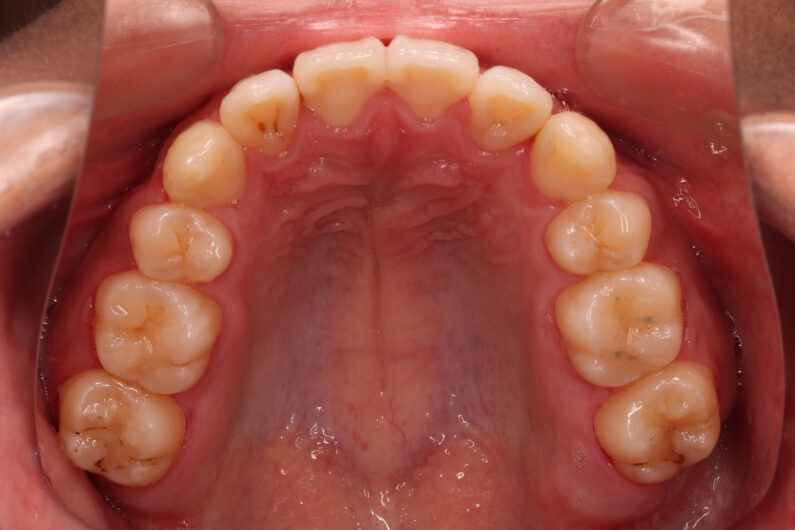

前歯部に重度の叢生(がたつき)のある患者さんです。

上顎の犬歯(八重歯)を小臼歯抜歯したスペースに移動させ配列しました。

下顎の抜歯スペースは、左側にずれている下顎の正中を補正する為に使用しました。

26回調整でしたが、学校や習い事のため、来院間隔が長く、動的治療期間3年4か月です。